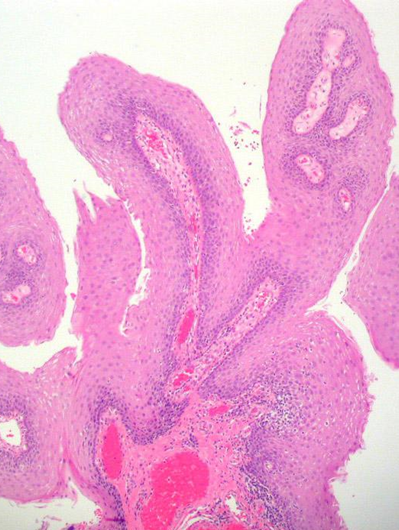

HPV感染后导致细胞增生呈现“乳头状”突起